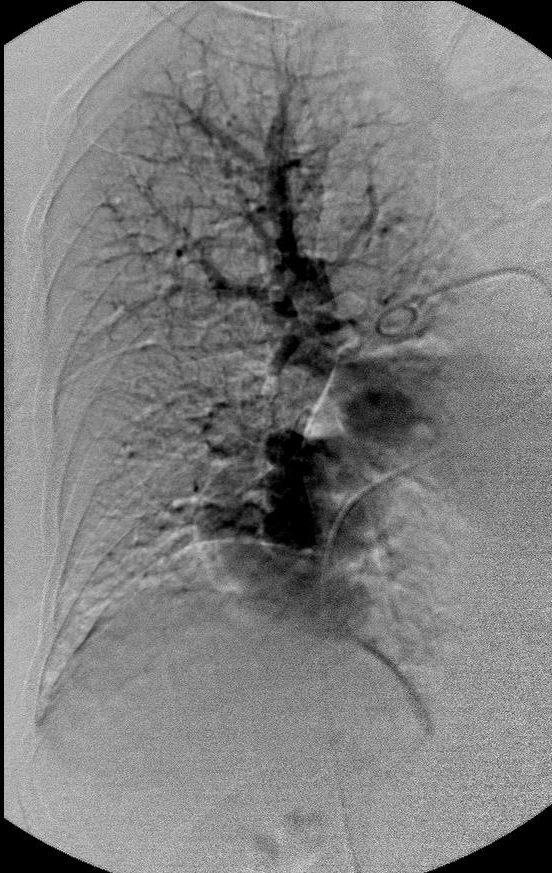

|

|

|

|

研究静脉池出口情况 |

寻找最佳工作位 |

静脉池出口直径大 |

|

|

|

|

静脉池出口直径大 |

放弃静脉池栓塞,仅栓塞滋养动脉 |

完成任务 |